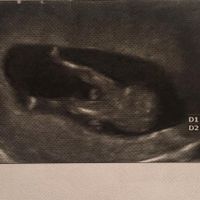

Ragazze secondo voi di che sesso saranno? Cosi per divertirsi un po' ☺

Ragazze che vi sembra da qst ecografia ??? Fatevi avanti!!! Io nn so cm fare a capire !!!